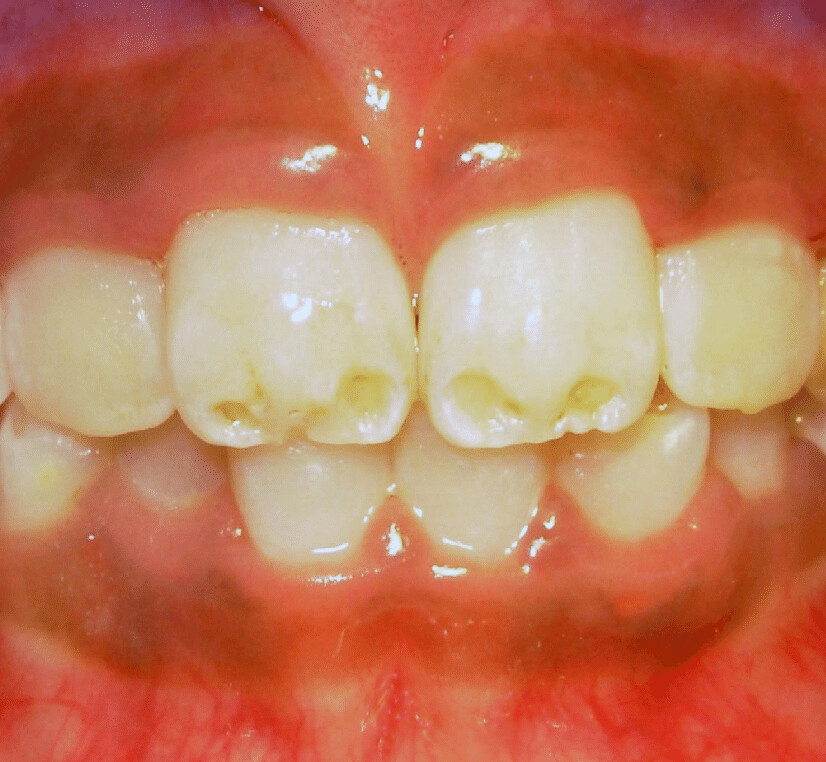

Enamel hypomineralisation happens when the mineralisation process is not fully achieved, resulting in discoloured enamel. This condition also weakens the teeth, which means that teeth can break down. The Australian Academy of Pediatric Dentistry also explains that hypomineralisation is prevalent in a fifth of all children. It can appear as discoloured patches of soft or decaying, bumpy enamel that usually affect the molars and incisors as they grow in. Teeth with hypomineralisation are sensitive and can cause children pain when eating; these teeth typically start to deteriorate once they grow in.

On the other hand, enamel hypoplasia is a condition where teeth have pits, grooves, and missing enamel. It can also result in smaller teeth. Hypoplasia appears as brown or yellow stains and exposed dentin. While the enamel is still hard, it is weak. This is a type of amelogenesis imperfecta, where the enamel on teeth is missing or severely thin and prone to breaking.

There are several causes as to how and why these conditions form. According to the Indian Journal of Dentistry, these conditions occur when there is a disturbance in the matrix formation of the teeth. To break that down, let’s look at ameloblasts, which are your teeth’s enamel-producing cells. These cells form in six stages: morphogenetic, organising, formative, maturative, protective, and desmolytic. Enamel hypoplasia happens in the formation stage, resulting in the pitting, grooving, or even total absence of enamel. Hypomineralisation happens in the maturative stage and can appear as “chalky” areas on your tooth’s enamel.